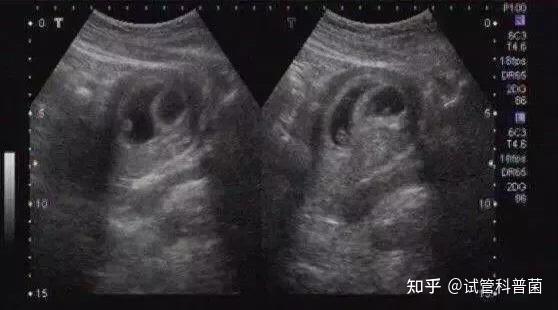

图片尺寸1000x382